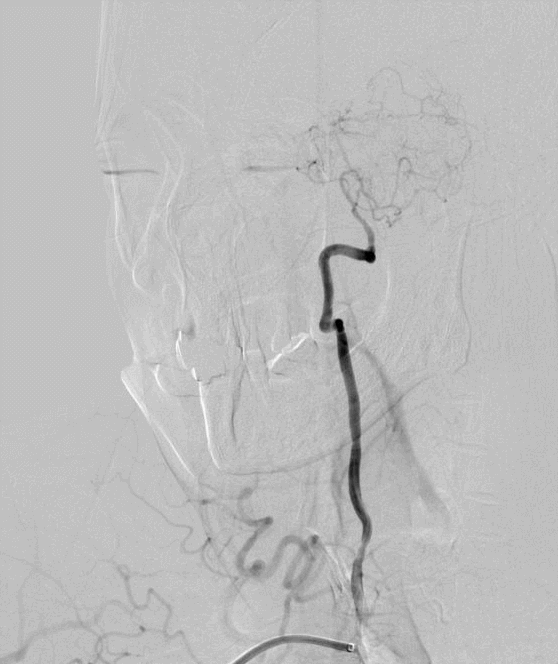

术前DSA

5F 125cm Sim2造影导管携5.5F Introsky X导管鞘成袢后超选左侧ICA。